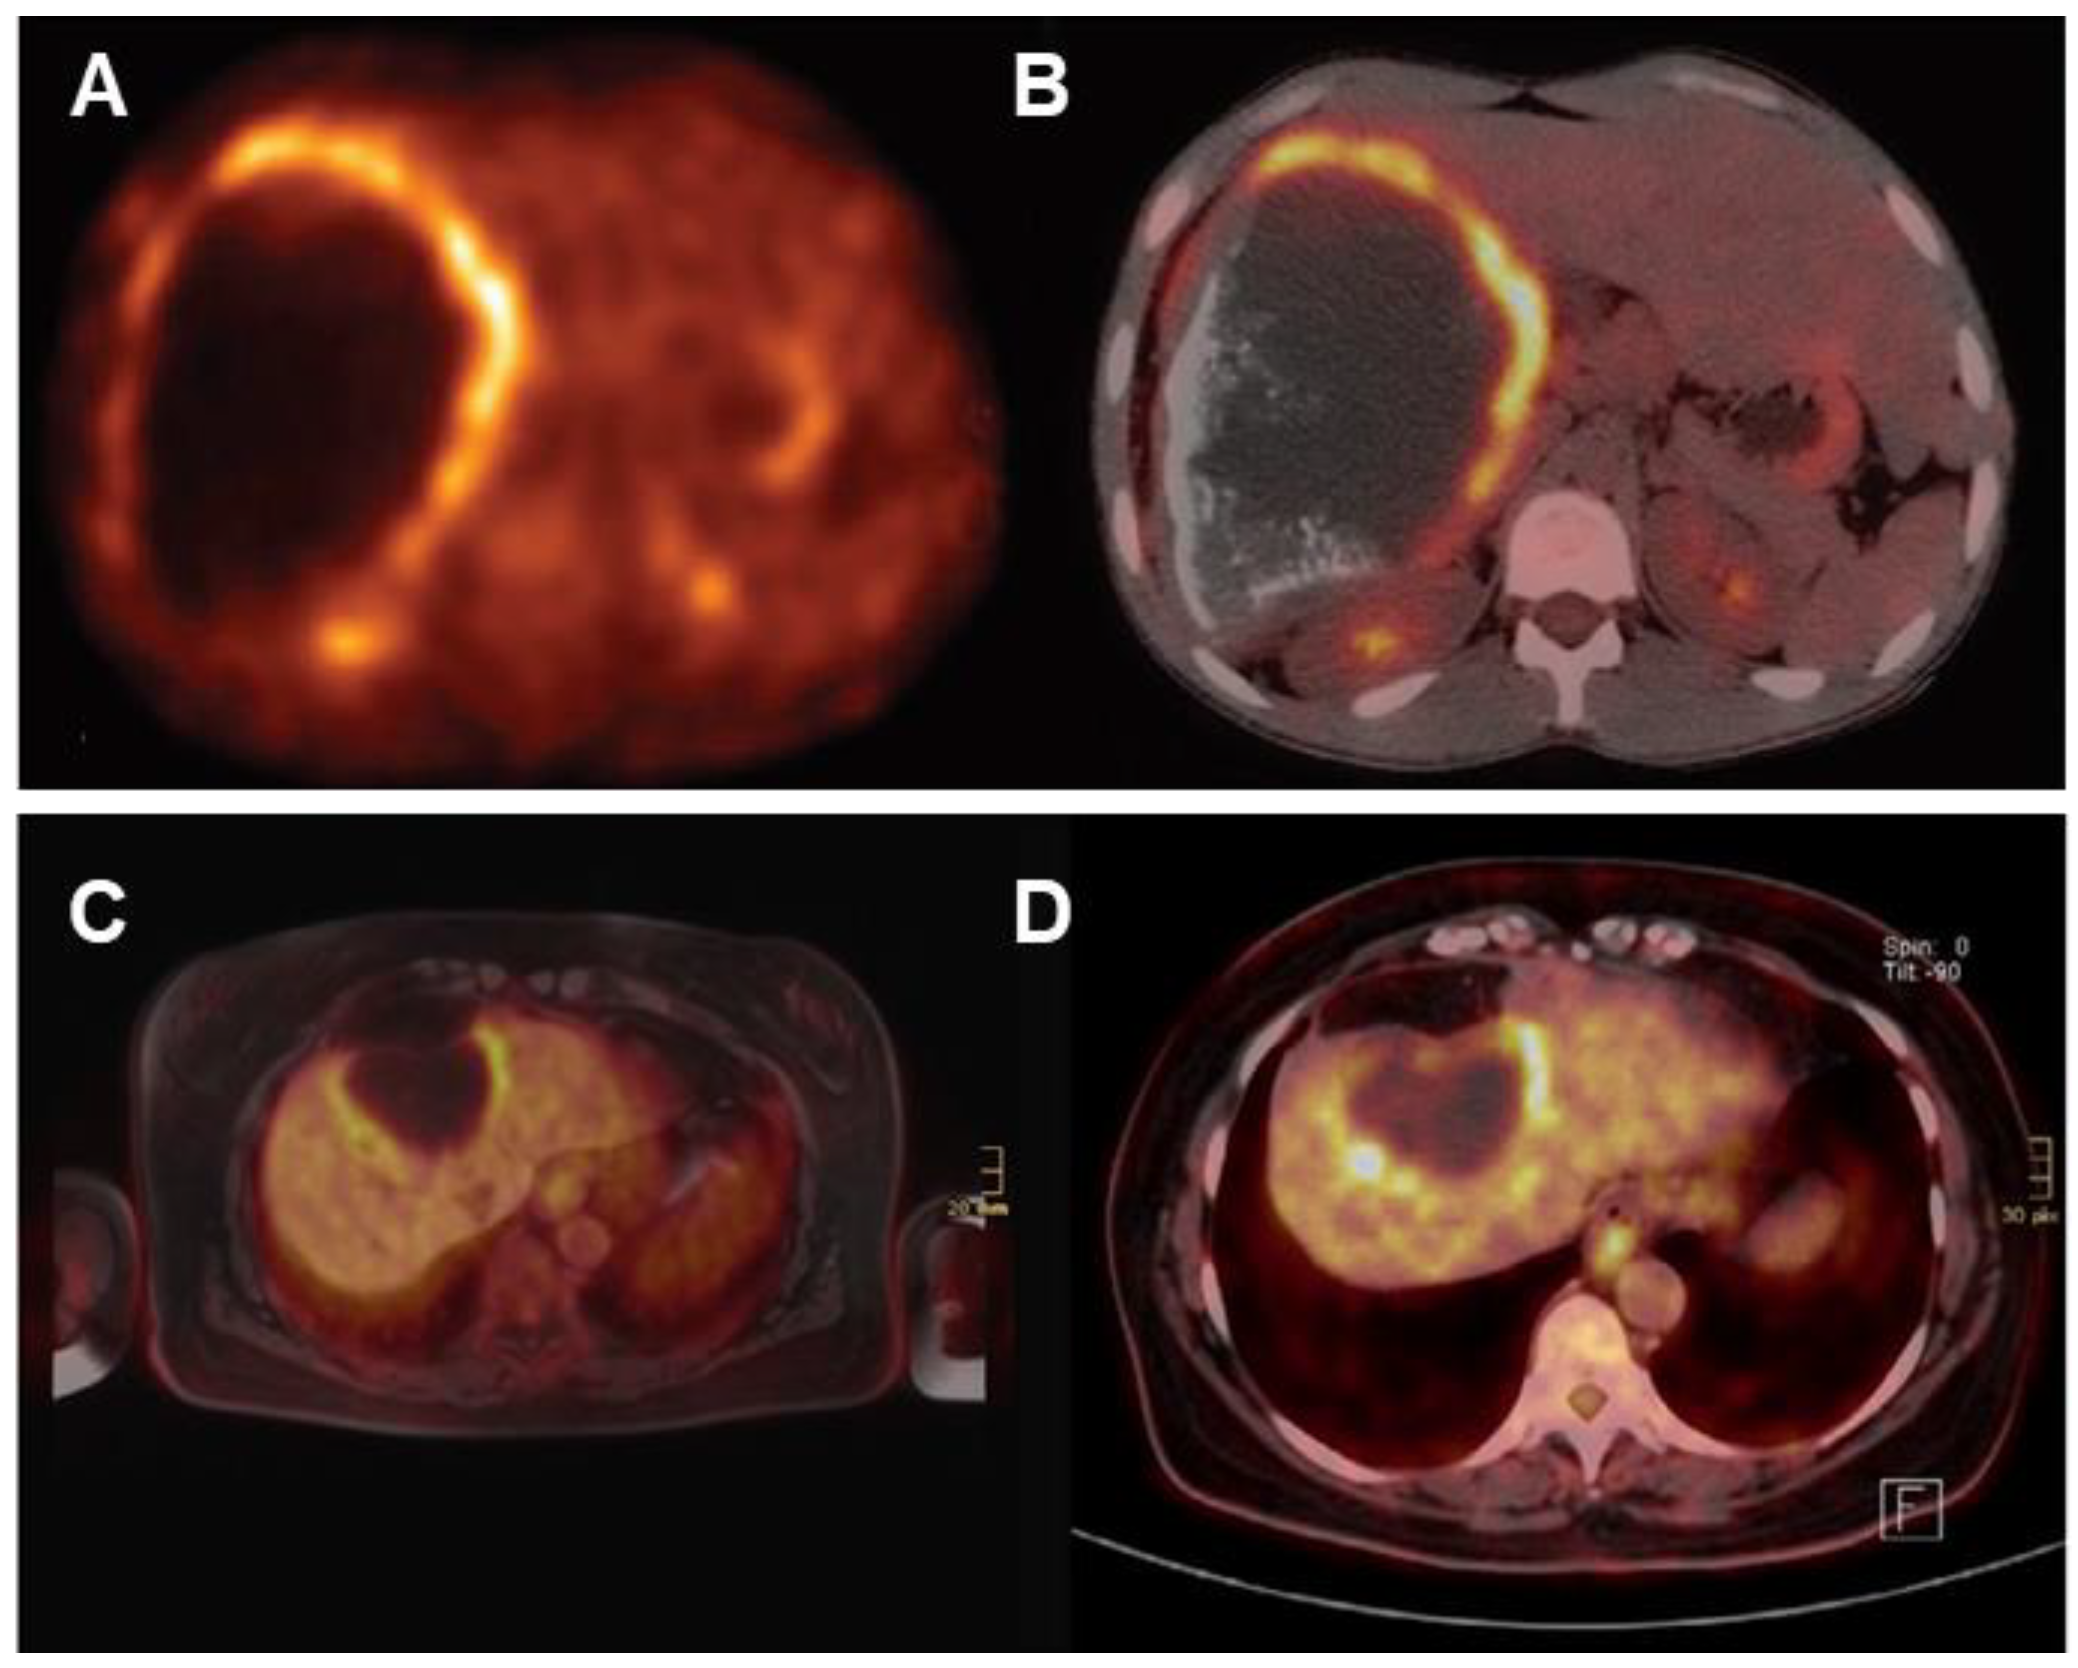

Glucose is the primary energy substrate for parasites and fluorodeoxyglucose positron emission tomography (FDG-PET) has been the gold standard for assessment of the metacestode activity status, which is essential for the individual treatment strategy of the AE patient [104,153,154]. FDG-PET was introduced 25 years ago to monitor the progression of AE lesions. Positive FDG uptake indicates active lesions, while negative FDG uptake suggests parasite abortion, an indication of albendazole withdrawal [155]. This method has proven to be effective, but there are cases of recurrence after discontinuation of medication in some patients [156]. Currently, the improved PET imaging protocol requires both the 3 h post-FDG injection delayed image and the 1 h post-injection image to be negative in order to determine that the result is negative [153]. Delayed imaging can reduce false negatives and enhance the sensitivity in determining the metabolic activity of AE (Figure 8).

As shown in Figure 9, in vitro experiments have demonstrated that immune cells surrounding the AE lesions exhibit high uptake of FDG, whereas parasitic cells within the cysts show low uptake of FDG [157,158,159,160]. Therefore, FDG-PET can indirectly assess parasite activity by monitoring the activity of host immune cells [161]. The metabolic hyperactivity of AE liver lesions on FDG-PET/CT is strongly correlated to the presence of microcalcifications on CT but not with the presence of macrocalcifications [84]. The absence of microcysts on MRI is closely associated with metabolically inactive diseases [138].